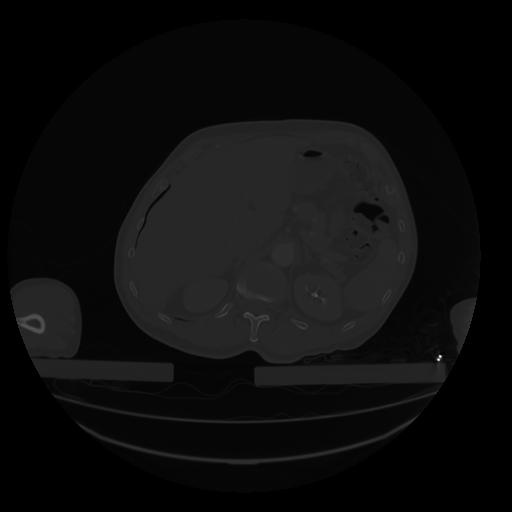

28 CUERPO,CE,Vol,2.0,CUERPO,,